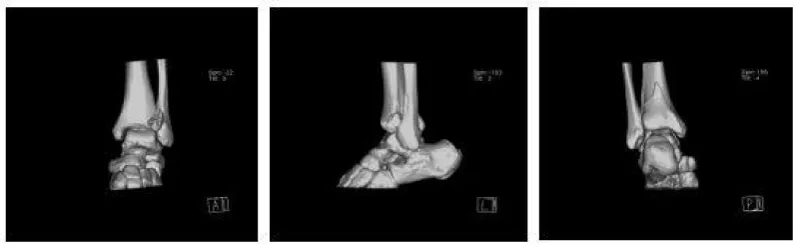

A 56-year-old woman was sent to the emergency department by her family. She sprained her left ankle when she went down the stairs. She had difficulty walking because of a painful left ankle. Specialized physical examination found tenderness in the anterolateral distal tibia and fibular neck. X-ray showed fractures in the tibia lateral border and fibular neck, with no evidence of inferior tibiofibular joint dislocation (Figures 1,2). A computed tomography scan confirmed the presence of Tillaux-Chaput and Volkmann fractures (Figures 3-5).

The anesthetic for the operation was lumbar anesthesia. A posterolateral approach was used to expose the Volkmann fracture. An anterior tibial approach was used to expose the Tillaux-Chaput fracture. The inferior tibiofibular joint was checked carefully. Fractures were reduced and then fixed. Volkmann fracture was fixed by buttress plate, and Tillaux-Chaput fracture was performed by hollow screw. Hook test intraoperative was negative. Anatomical reduction and perfect stability were confirmed by X and CT postoperatively (Figures 6.7). CT scan in the transverse section confirmed that the anterior and posterior edge of the distal fibula is in an arc with the fractures of the tibia. It meant there was no dislocation of the distal fibula. The anterior and posterior ligaments of the inferior tibiofibular ligament are in good condition.